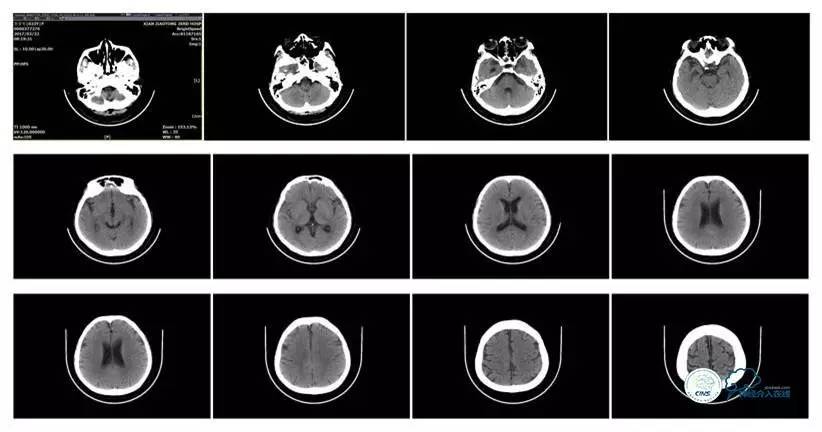

头颅CT

MRI T1

MRI T2

病史:患者于1年余前,因头部外伤在外院行头颅CT提示:未见异常。约3月后患者出现头痛、发作性意识丧失,在当地医院行头颅CT及MRI提示:未见明显异常。诊断为外伤性癫痫,予以对症治疗,未见明显好转。6月余前,无明显诱因出现鼻腔漏液,予以保守治疗,此后鼻腔间断漏液,漏液后头痛缓解。13天前因高热、恶心、呕吐在外院诊断为颅内感染(肺炎链球菌),予以抗炎等对症治疗2周后鼻漏停止,体温正常,CSF常规、生化正常,但头痛仍未缓解,转入我院神经内科治疗。反复腰穿颅内压450-500mmH2O左右,脑脊液常规及生化均正常。颅脑CT及MRI、MRV提示:左侧顶叶硬膜下血肿,鼻窦炎、乳突炎、左侧横窦、乙状窦闭塞、右侧横窦、乙状窦狭窄。予以华法林抗凝治疗2周,维持INR2-3,患者头痛仍无明显缓解,颅内压无下降,转入我科。